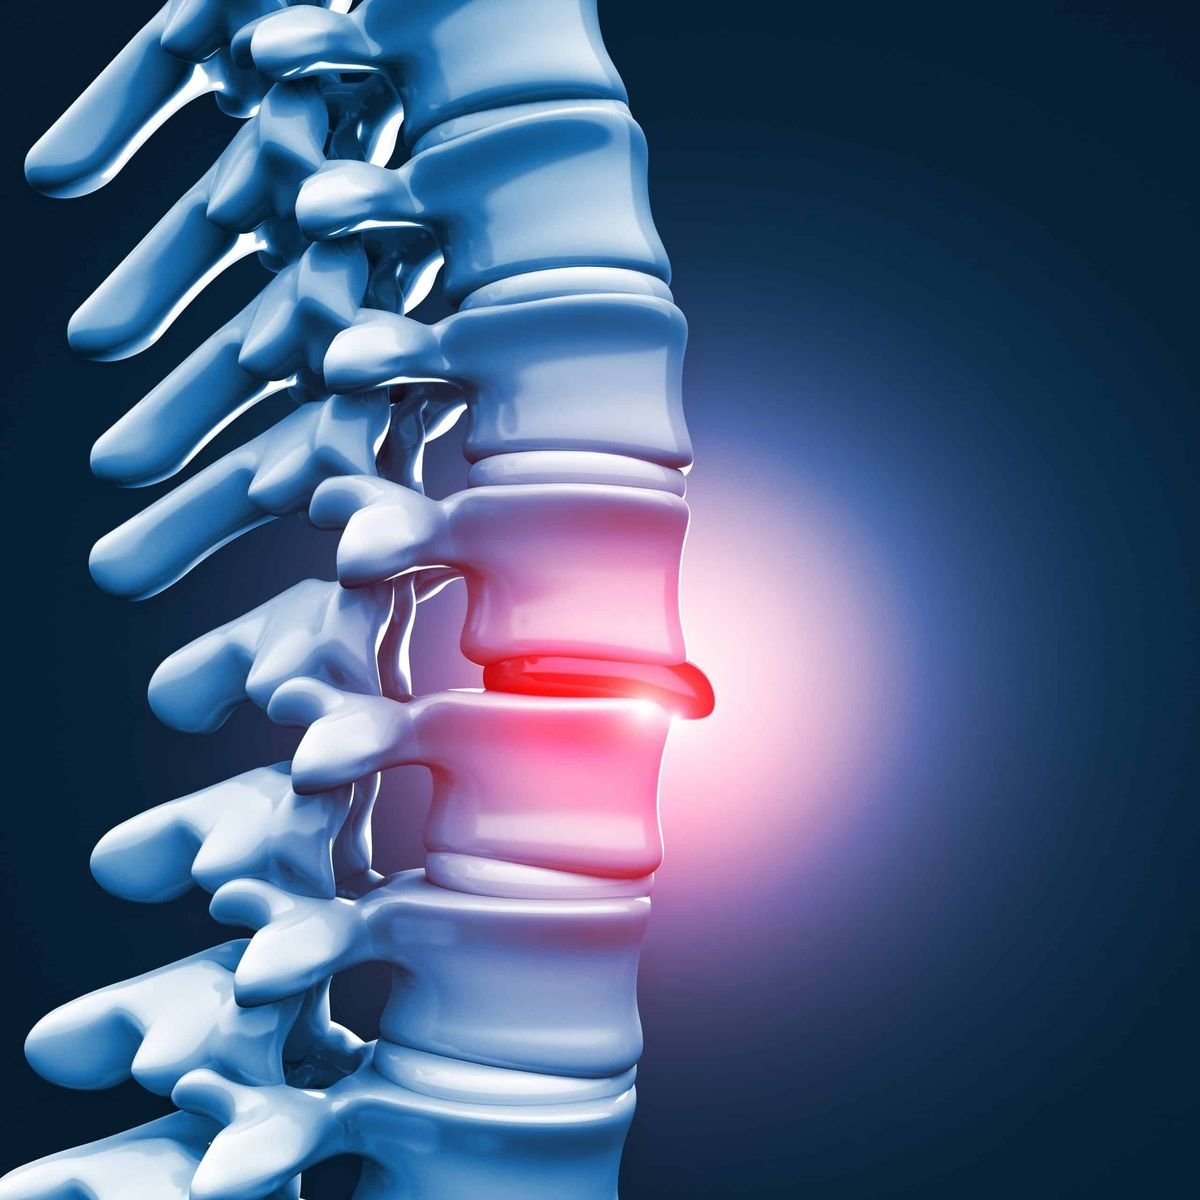

Disc problems involve spinal disc damage, causing back pain, nerve compression, and limited movement.